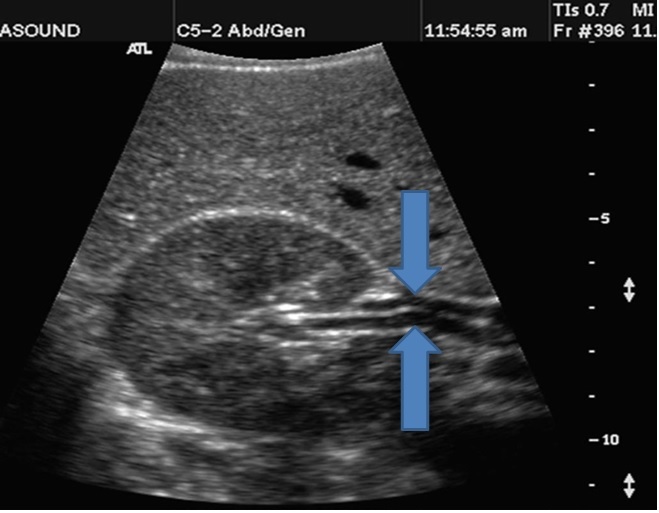

From top down label the structures

1. Right Renal vein

2. Right Renal artery